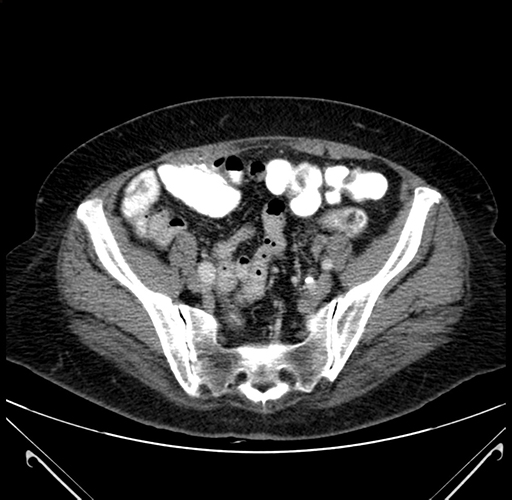

Pre-Chemo: Axial Venous

Axial Venous